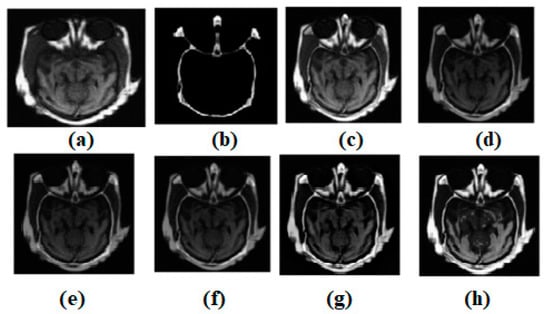

Using the MATLAB version R2022a software, the experimental evaluation is complete. A resolution of 512 × 512 is used for the experimental results of all the images. There are numerous multi-modality effects observed in Figure 3, Figure 4, Figure 5, Figure 6 and Figure 7. Input source images are shown in Figure 3a,b. Non-conventional methods, such as [44,47,49,51,53], are combined with the established structures in all images. Figure 3c–g depicts the effects of [44,47,49,51,53], respectively. Similarly, ref. [53] different modalities are also being investigated in MR-T2 images and SPECT images. In Figure 3, the result of ref. [44] is satisfactory; however, in terms of edge preservation and texture preservation, the result of ref. [44] is not satisfactory. However, the contrasts are well-preserved. In some homogenous areas, the texture is also well-preserved. However, sharpness in the heterogeneous area is missing. In Figure 3, the result of ref. [47] is acceptable; nevertheless, when it comes to the preservation of edges and textures, the result of ref. [47] falls short of expectations. Nevertheless, the contrasts have been maintained very well. There are some areas of homogeneity, and the texture has also been nicely conserved. However, there is a lack of brightness in the heterogeneous area. In Figure 3, the outcome of ref. [49] is satisfactory; nevertheless, when it comes to the maintenance of edges and textures, the result of ref. [49] does not live up to expectations. Nevertheless, the contrasts of ref. [48] have been preserved quite beautifully. There are some places of homogeneity, and the texture has also been carefully preserved. There are also other areas where the texture has changed. The heterogeneous region, on the other hand, has an inadequate amount of light. In Figure 3, the result of ref. [51] is satisfactory; nevertheless, when it comes to the maintenance of the image’s edges and textures, the result of ref. [51] does not live up to expectations. Nevertheless, the contrasts have been maintained quite well throughout. There are certain regions of consistency, and the texture has also been maintained in an admirable fashion. On the other hand, the heterogeneous region suffers from a lack of brightness. In Figure 3, the result of ref. [53] is fine, but it falls short when it comes to keeping edges and textures. Nevertheless, the differences have been maintained in a really good way. There are some areas where everything looks the same, and the texture has also been maintained well. However, the area that is not homogenous is not very bright.

Figure 3.

Multi-modality medical image fusion results (a) Source image: CT, (b) Source Image: MR, (c) Result of [44], (d) Result of [47], (e) Result of [48], (f) Result of [49], (g) Result of [51], (h) Result of [53].